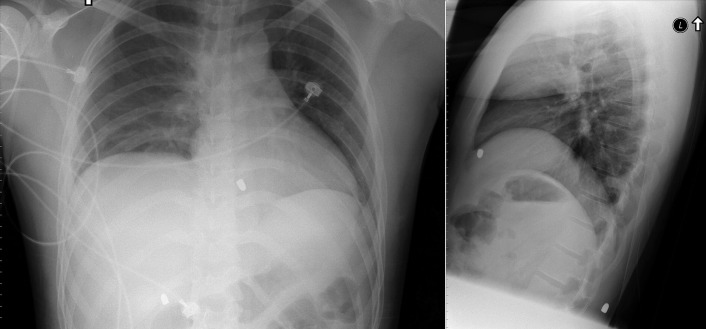

Of all traumatic lesions to the thoracic cardiovascular system, the most predictable one is blunt deceleration/acceleration traumatic injury to the thoracic aorta, resulting in a false aneurysm-type lesion, typically of the isthmus proximal descending aorta. It may also involve the ascending aorta, the supradiaphragmatic aorta, or the innominate artery take-off ( Figs. 28-1 to 28-13 ).